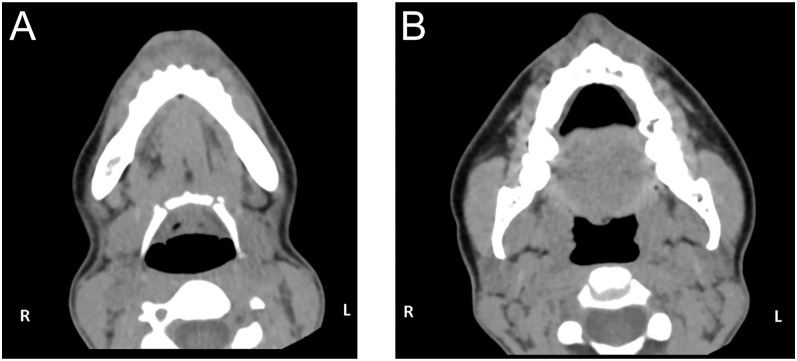

Abstract Image